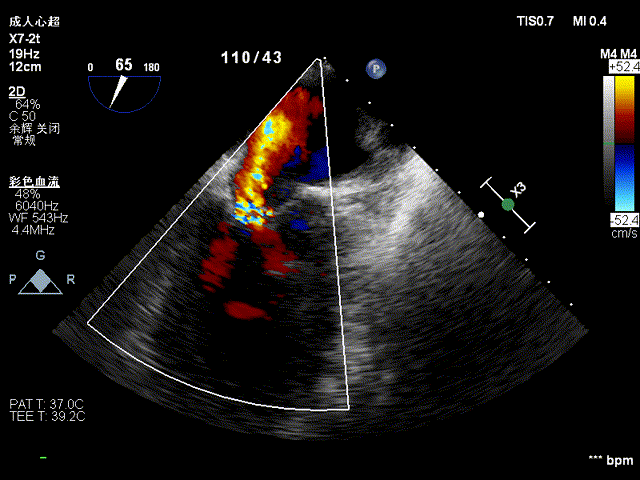

二尖瓣中大量反流:

全超声引导下TEER

导丝进行房间隔穿刺:

CDS放置在二尖瓣处:

打开夹子,调整弹道垂直于二尖瓣瓣环:

将MitraClip推进至左心室,捕获瓣叶:

捕捉瓣叶后,经超声心动图确认瓣叶夹持牢固,释放瓣膜夹: